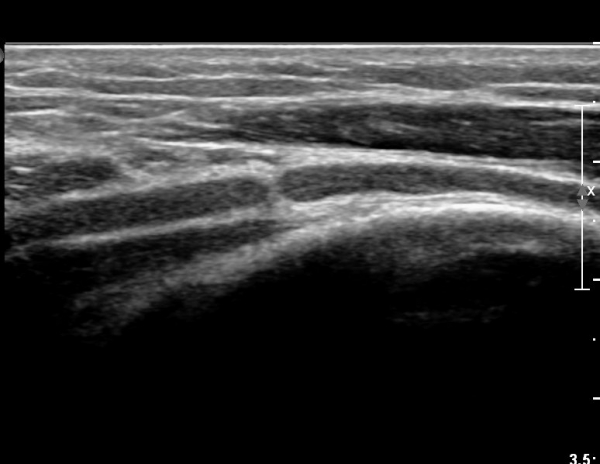

ÃÊÀ½ÆÄ°Ë»ç

¿ä°ñ °í¶û¿¡¼ ¿ä°ñ½Å°æ Ⱦ´Ü¸é°Ë»ç»ó ¿ä°ñ½Å°æÀÇ °æ¹ÌÇÑ Àú¿¡ÄÚ ºÎÁ¾ÀÌ °üÂûµÈ´Ù(»çÁø 2).

ŽÃËÀÚ¸¦ Á¶±Ý ¸»´ÜÀ¸·Î À̵¿ÇÏ´Ï ¿ä°ñ½Å°æ Àú¿¡ÄÚ ºÎÁ¾ÀÌ ´õ¿í ¶Ñ·ÈÇѵ¥(»çÁø 2),